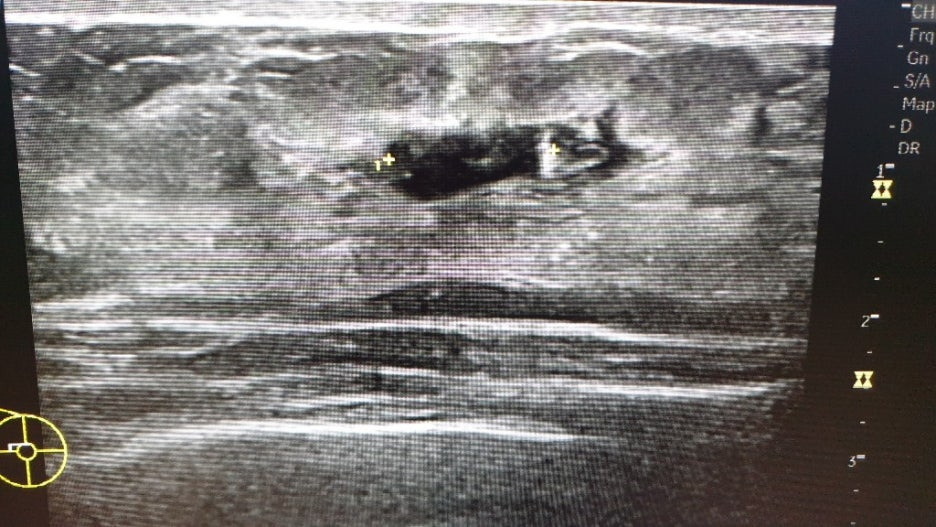

그다음은 유방 초음파를 하는데 팔을 위로 올린 상태로 검사를 해요. 엑스레이에서 왼쪽에 혹이 보였기 때문에 꼼꼼하게 봐 주셨어요.

힐끗힐끗 화면을 보니 작고 둥근 것들이 보였고, 여러 번 길이를 재는 것이 보였어요. 엑스레이 상으로는 깨끗했던 오른쪽 가슴에도 혹이 보였어요. (점점 불안해지기 사작했습니다...)

왼쪽 2.3cm / 오른쪽 1.4cm + 기타 작은 혹 몇 개

크기보다 모양이 더 중요하다고 하더군요. 일단 동글동글하면 괜찮은 것이고 뾰족뽀족하게 생기면 악성일 가능성이 크다고 합니다.

모양이 나쁘지는 않지만 크기가 1cm 이상이면 작은 것은 아니므로 조직 검사를 하자고 하더군요. 조직 검사를 해서 이 혹이 어떤 혹인지 정확하게 확인 후 치료 방법 등을 생각해 보자고 하셨어요.